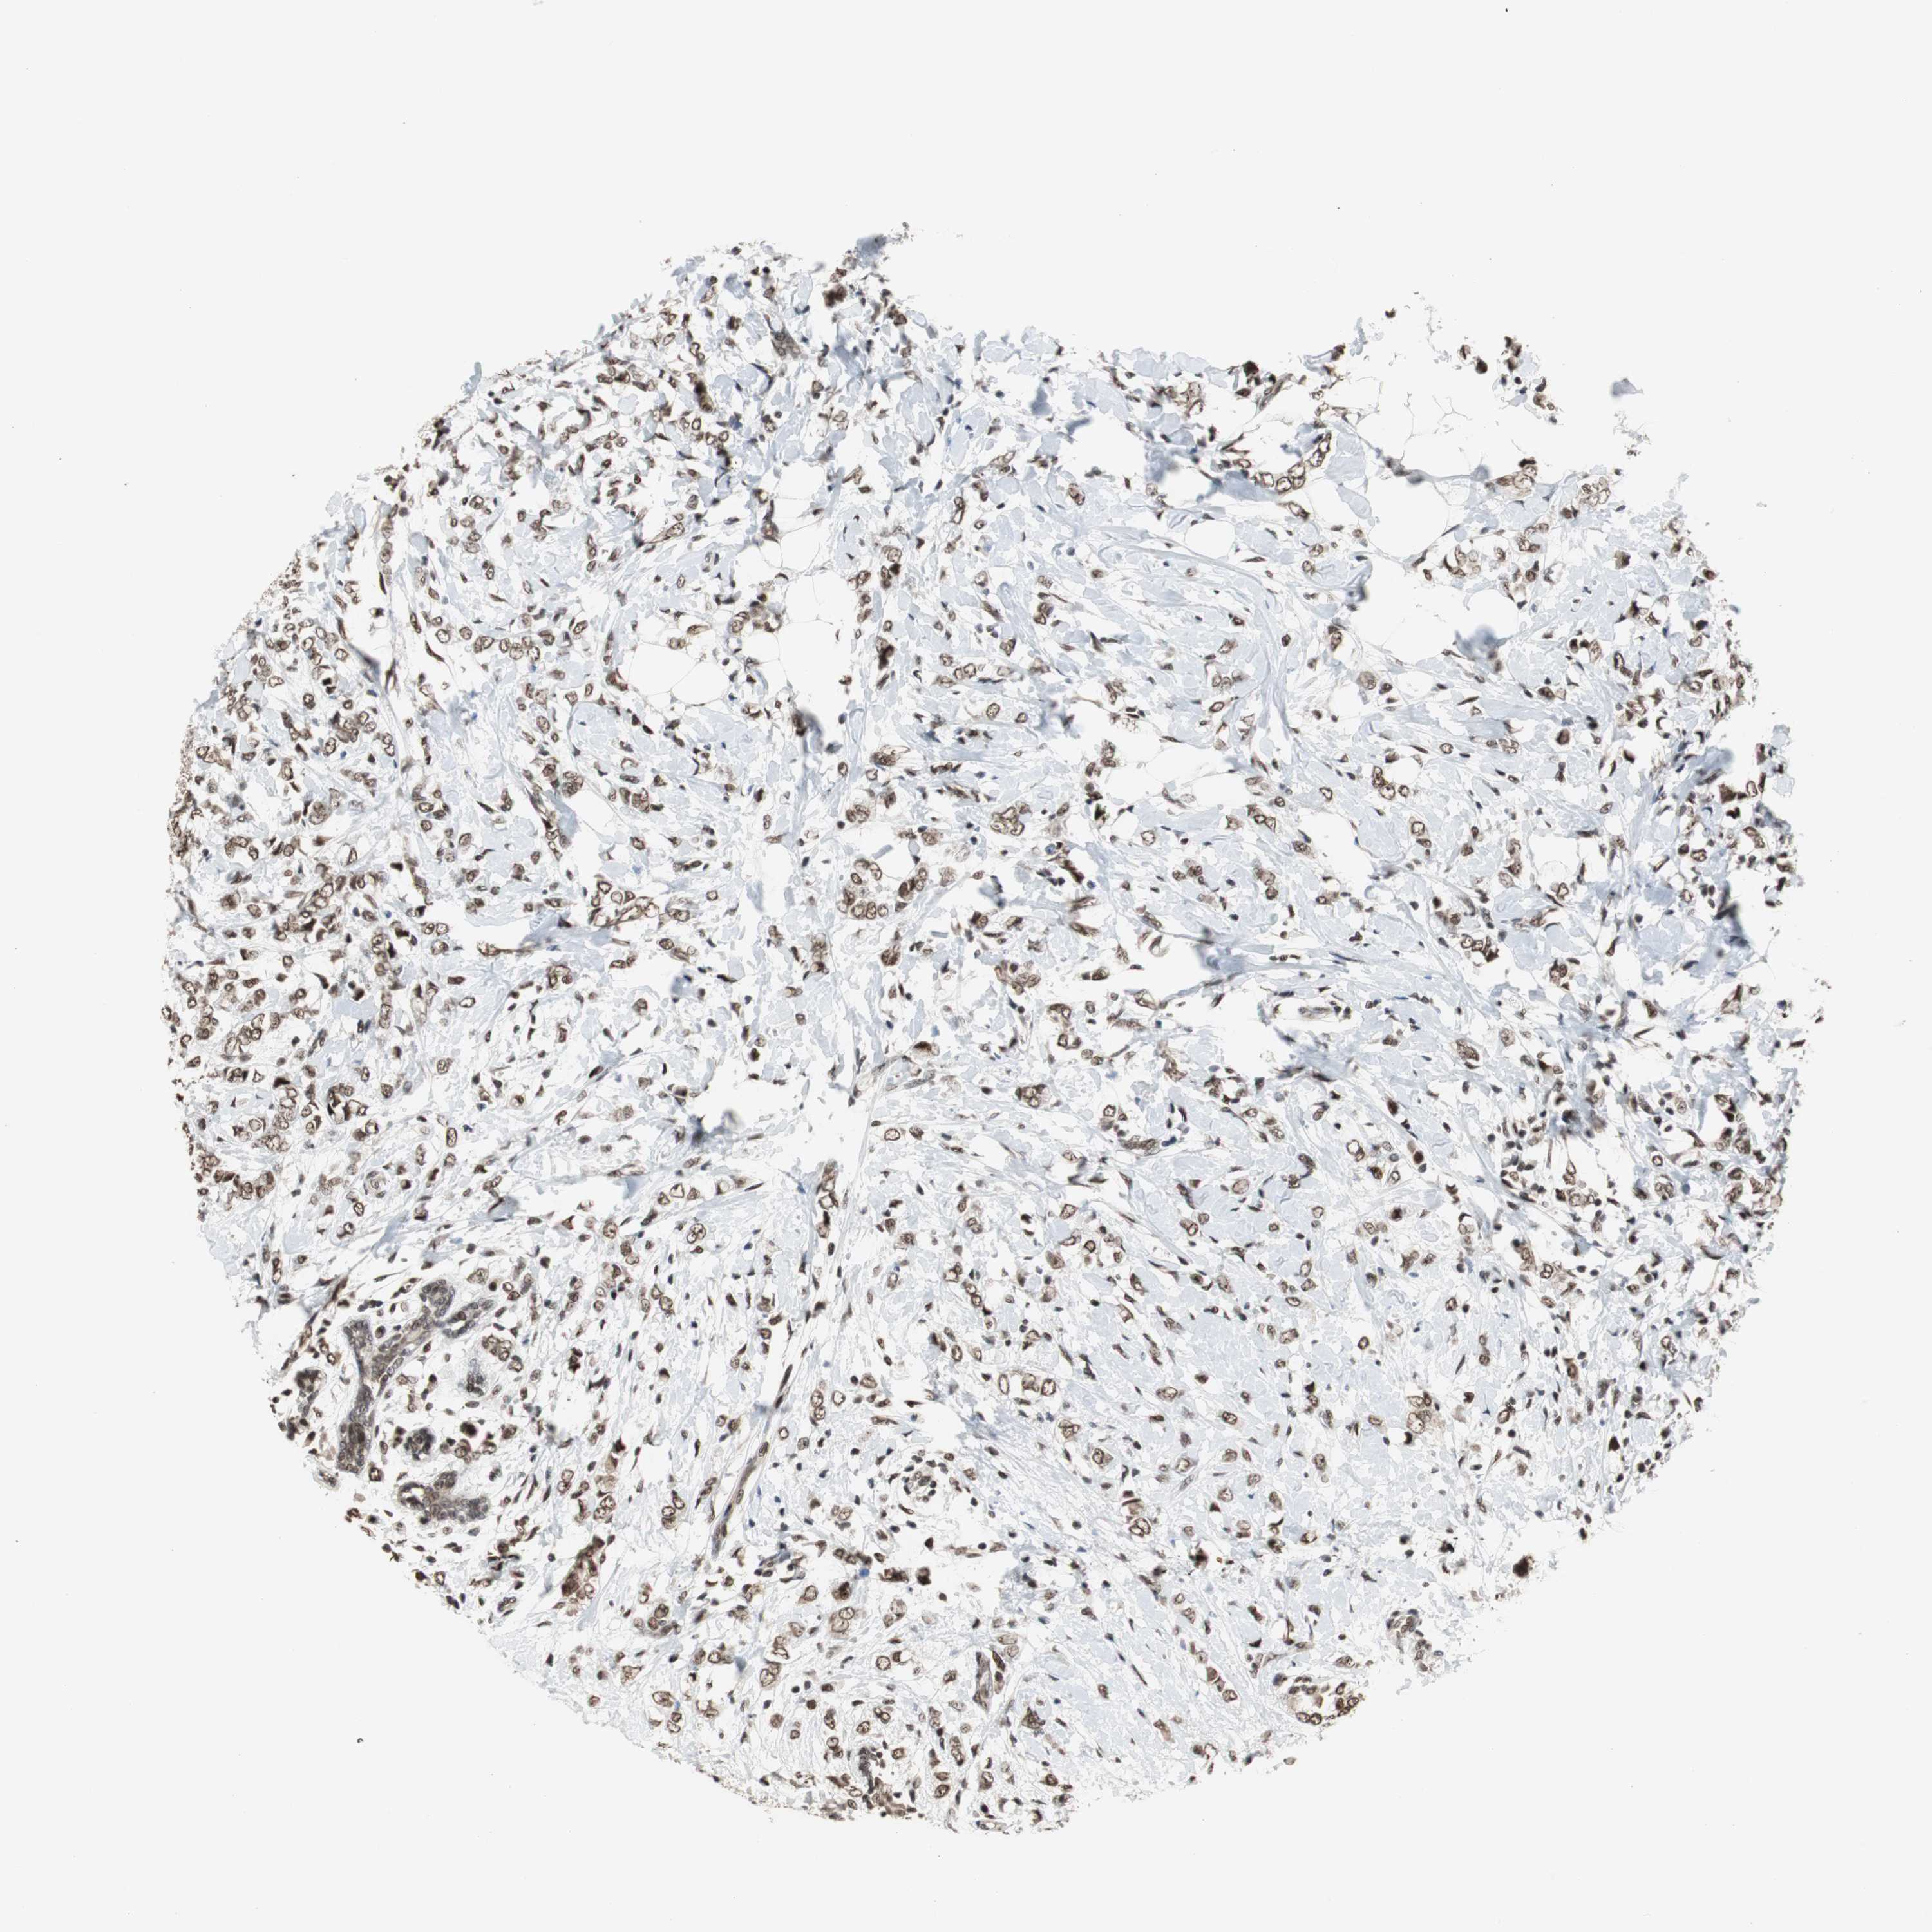

CANCER BREAST CANCER Show tissue menu

BRCA TCGA BRCA VALIDATION PROTEIN EXPRESSION